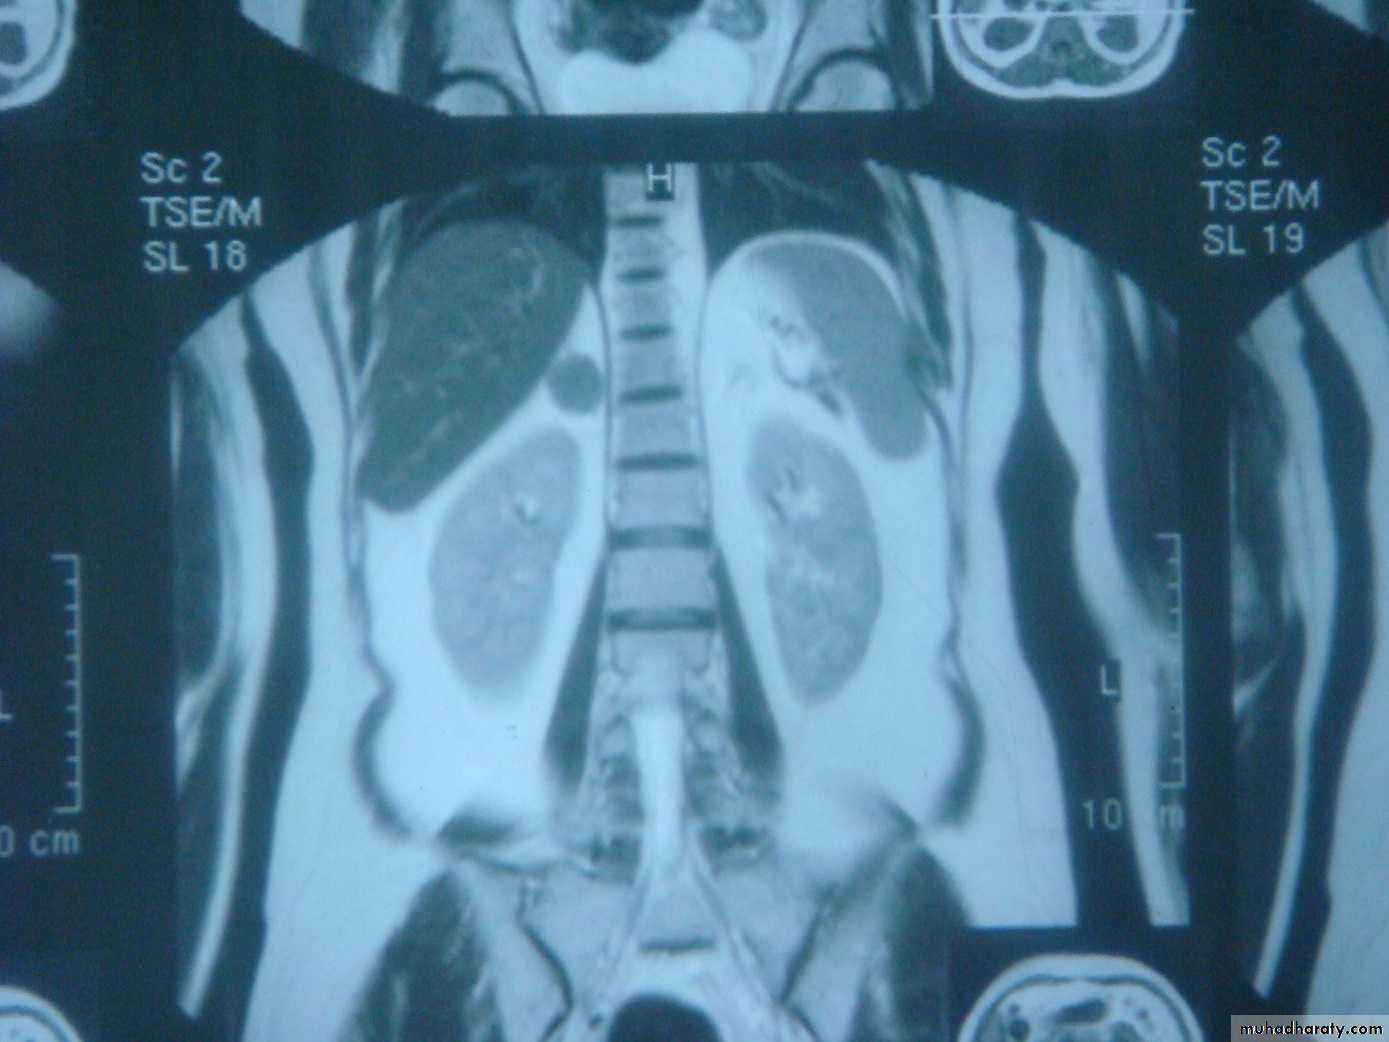

MRI or CT should be performed to distinguish unilateral from bilateral disease

In patients with suppressed ACTH levels, a CT or MRI scan is performed to assess the adrenal glands.

2- imaging study for the localization of the phaeochromocytoma and/or metastases. MRI is preferred because contrast media used for CT scans can provoke paroxysms.

CT/MRI of the chest and abdomen, a bone scan.